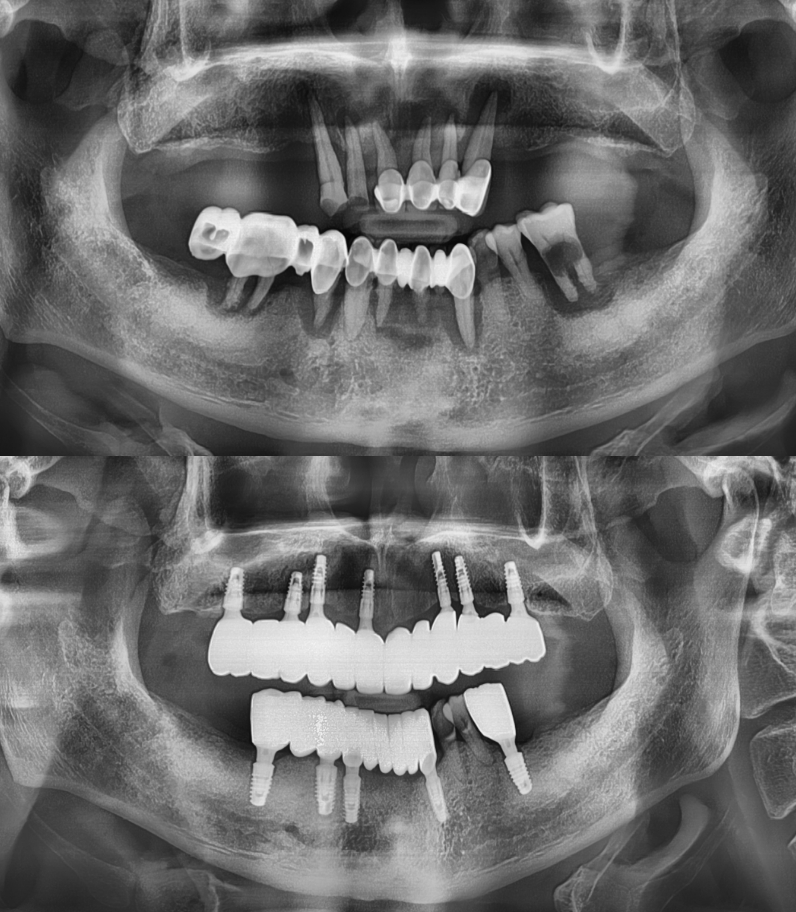

임플란트 전/후

실제 케이스

성공적인 임플란트 치료는 세밀한 분석과

그에 맞는 치료가 중요하기에

다수의 치료 경험을

보유한 의료진이 상주한 곳에서 시작하시기 바랍니다.

임플란트

환자 성함 : 권**

치료기간 : 2023.06 - 2024.07 (1년 1개월)